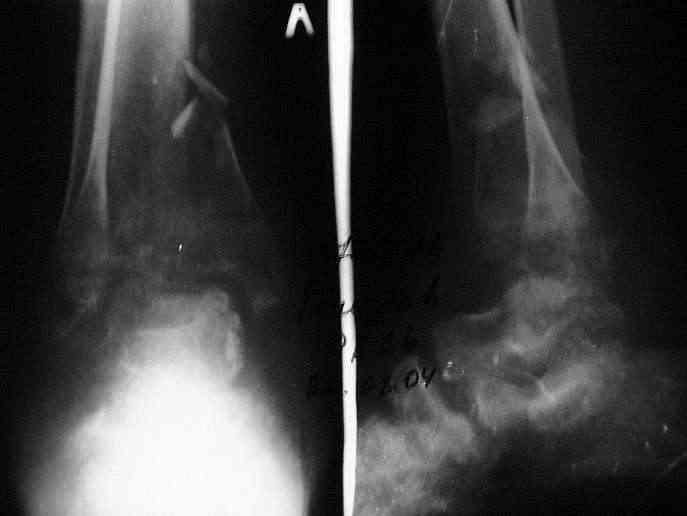

Здравствуйте, коллеги.Больной 26 лет, в 2004 году попал ко мне с диагнозом:синтезированный в аппарате Илизарова неполный внутрисуставной оскольчатый перелом дистального метафиза левой большеберцовой кости со смещением; выраженный остеопороз; множественное спицевое нагноение. Несостоятельность фиксации (костные отломки буквально "елозили" по спицам, несмотря наналичие упорных площадок).

Мной был демонтирован АВФ, удалены все спицы. Больной некоторое время лечился консервативно (шина Белера, антибиотики, перевязки). По заживлению и купировании гнойно-воспалительного процесса была произведена осткрытая репозиция, накостный остеосинтез 1/3 трубчатой пластиной.Такой вариант был принят из-за жуткого остеопороза и отказом больного от предложенного артродезирования голеностопного сустава сразу. Послеоперационный период без особенностей. Через год, больной пришел на осмотр на своих двоих, без дополнительной опоры, с жалобами на боли приходьбе в обл. г/стопа и с желанием замкнуть сустав. В операционной столкнулся с неожиданной проблемой по удалению пластины, она была глубоко вмурована в толщу склерозированного метафиза на глубину 1.5 см; удалить не рискнул (считал, что металл помешает в ходе реконструкции и требуется его удаление).